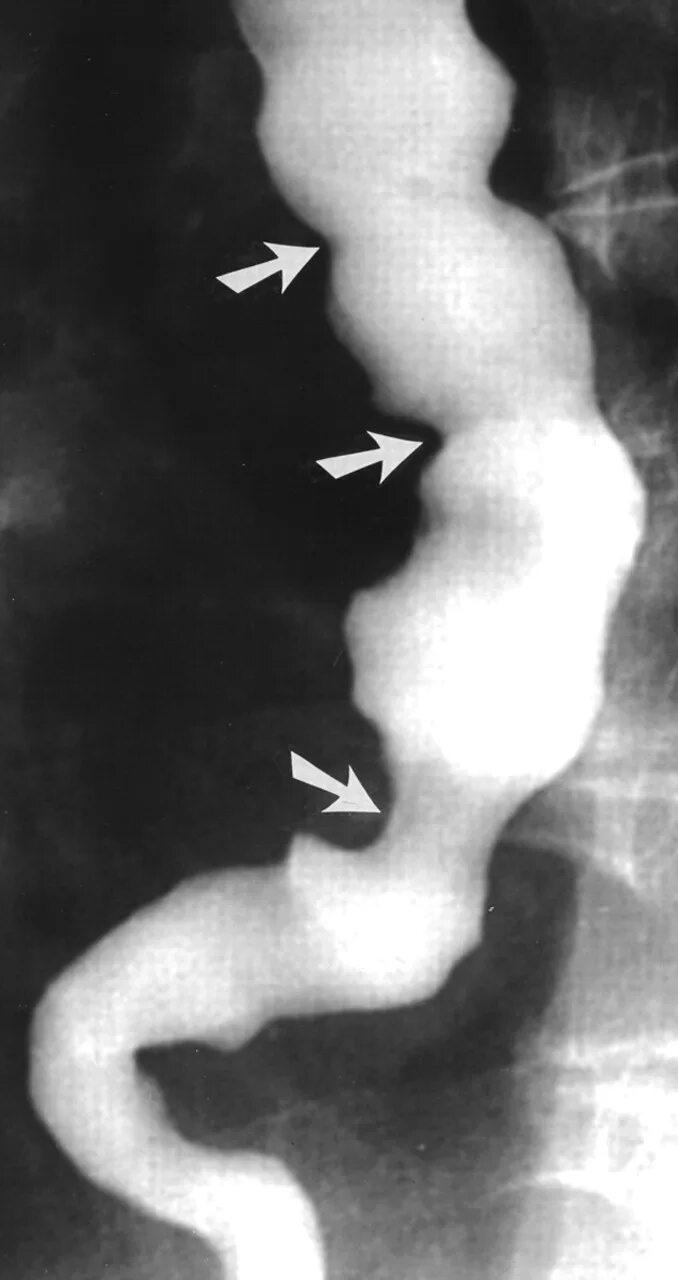

Диффузный эзофагоспазм